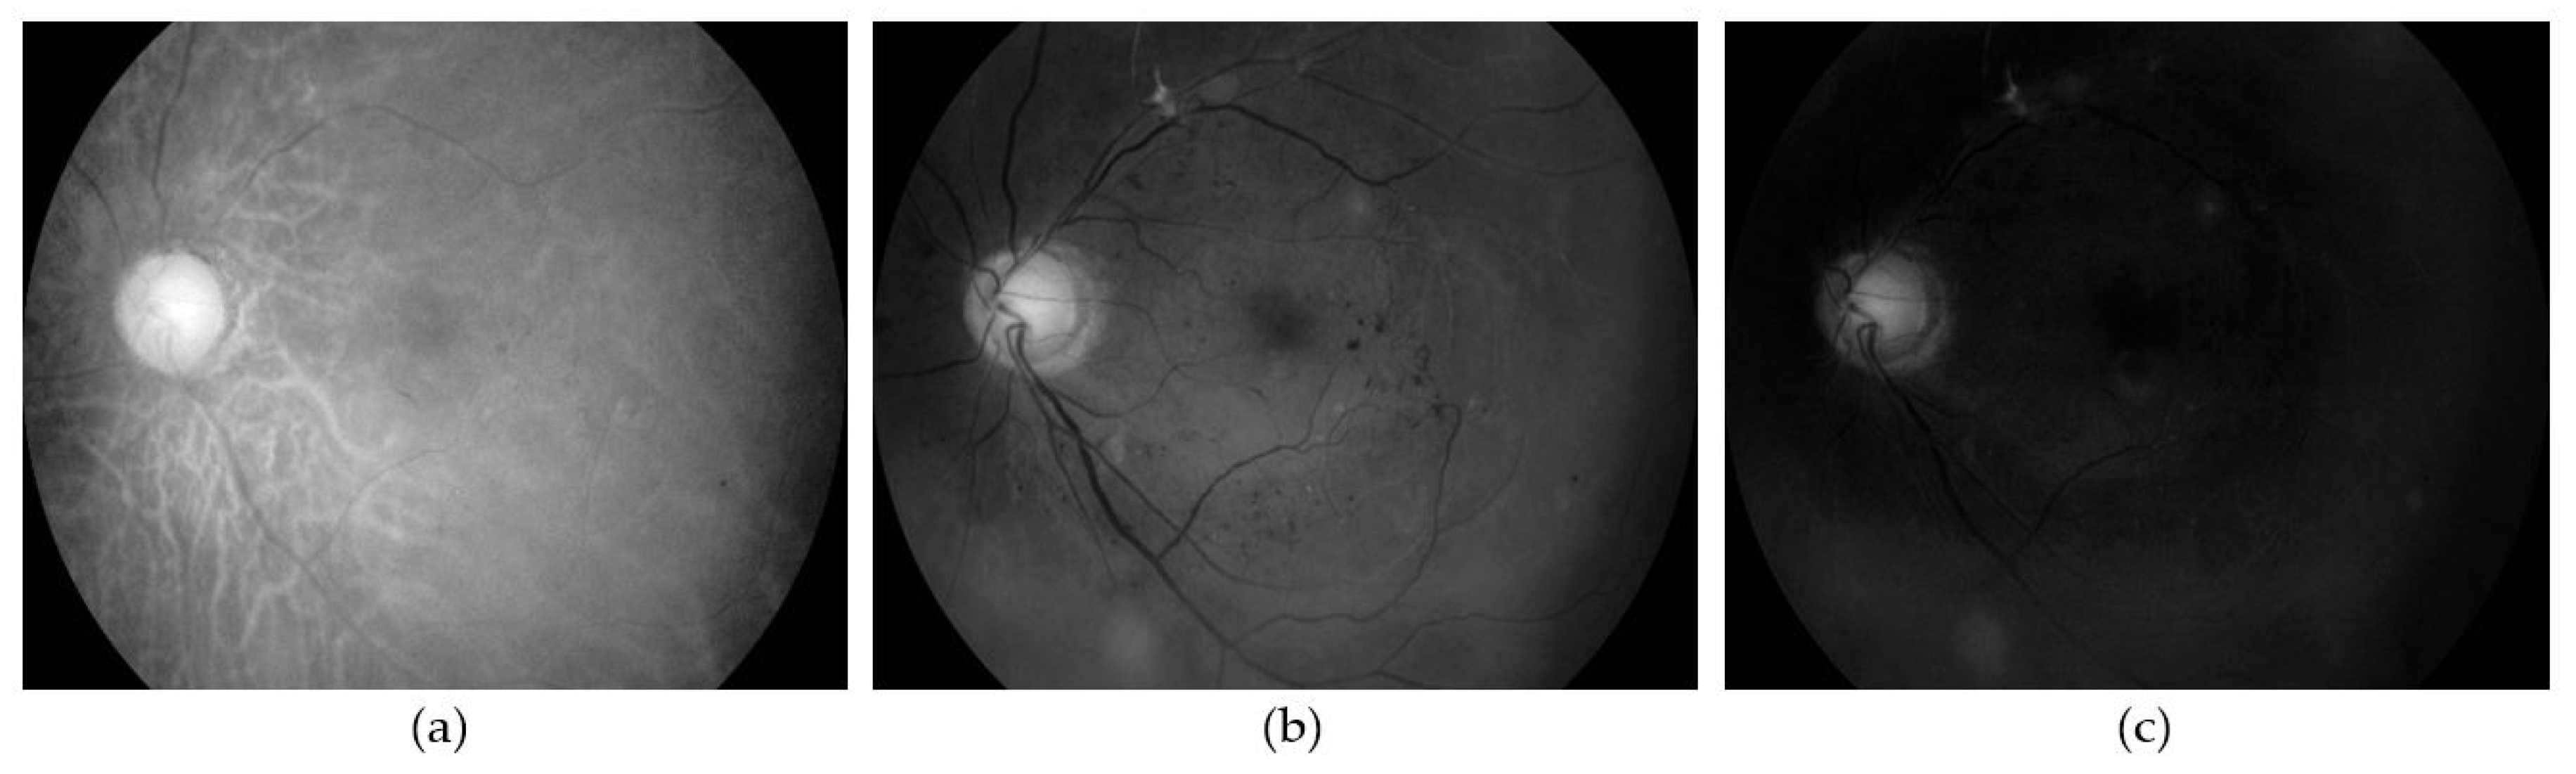

3.1. Image Pre-Processing and Data Preparation